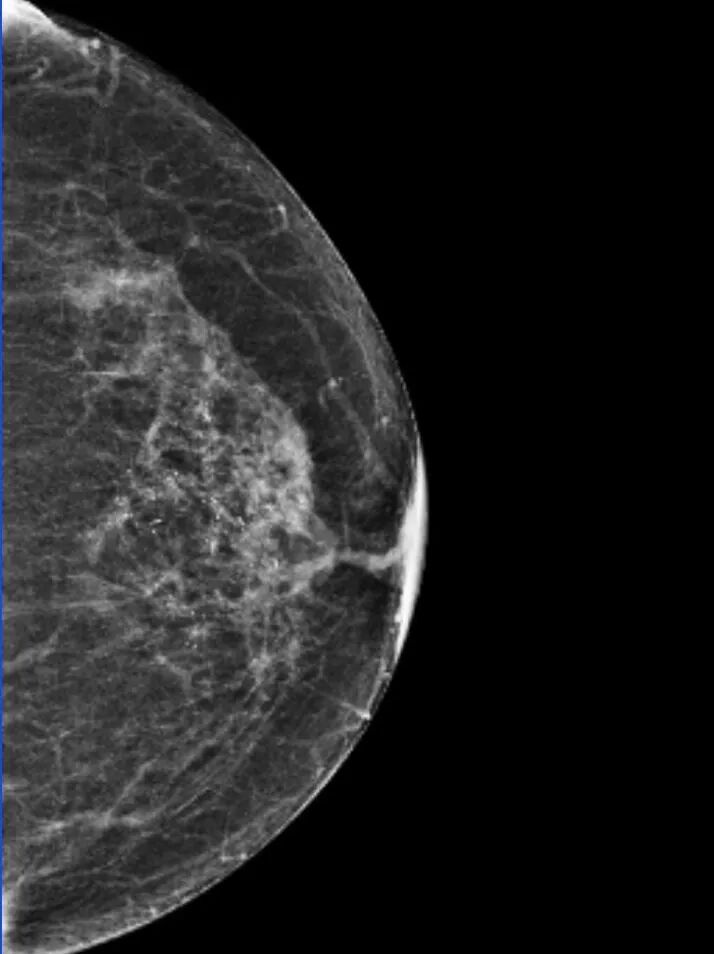

钼靶提示:左乳上部及中央区段样分布细小多形性钙化灶,拟 BI - RADS 4b类,请结合临床,建议活检;

左乳中央区前带局灶性不对称, BI - RADS 0类,建议 MR 检查;

左乳头凹陷。